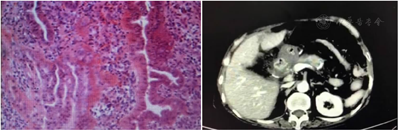

手术时间280 min,术中出血量50 ml,未予输血。术后病理报告:胰头慢性炎;胰管扩张,胰管内见增生性息肉(图10)。术后有胆漏,量100~200 ml/d;术后2周带管出院。无术后出血、胰瘘、十二指肠瘘、胆总管狭窄等并发症。术后2个月复查CT,结果满意(图11)。